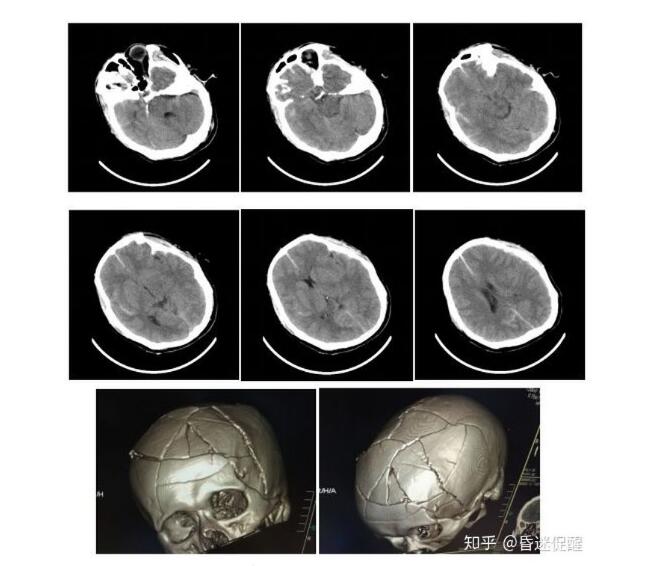

头部CT提示:弥漫性轴索损伤、左侧额颞顶硬膜下少量出血、蛛网膜下腔出血、颅骨粉碎性骨折。

入院时情况(2018-01-10)